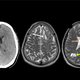

Več mesecev je 52-letni moški trpel zaradi hudih migren. Slikanje glave je razkrilo presenetljiv vzrok njegovih težav. 52-letni moški s Floride je imel hude težave z migrenami. Močni glavoboli so … · Žurnal24 · 1L

52-letni Američan se je odločil poiskati zdravniško pomoč, ko so se njegove migrene začele pogosteje pojavljati in so bile vse bolj intenzivne, običajna zdravila pa niso prinesla olajšanja. Presenetljivo je … · Regional · 1L

Moški s Floride je obiskal svojega osebnega zdravnika, saj je v zadnjih štirih mesecih doživljal vedno pogostejše migrene. Dejal je, da njegova zdravila ne delujejo več. · Slovenske novice · 1L